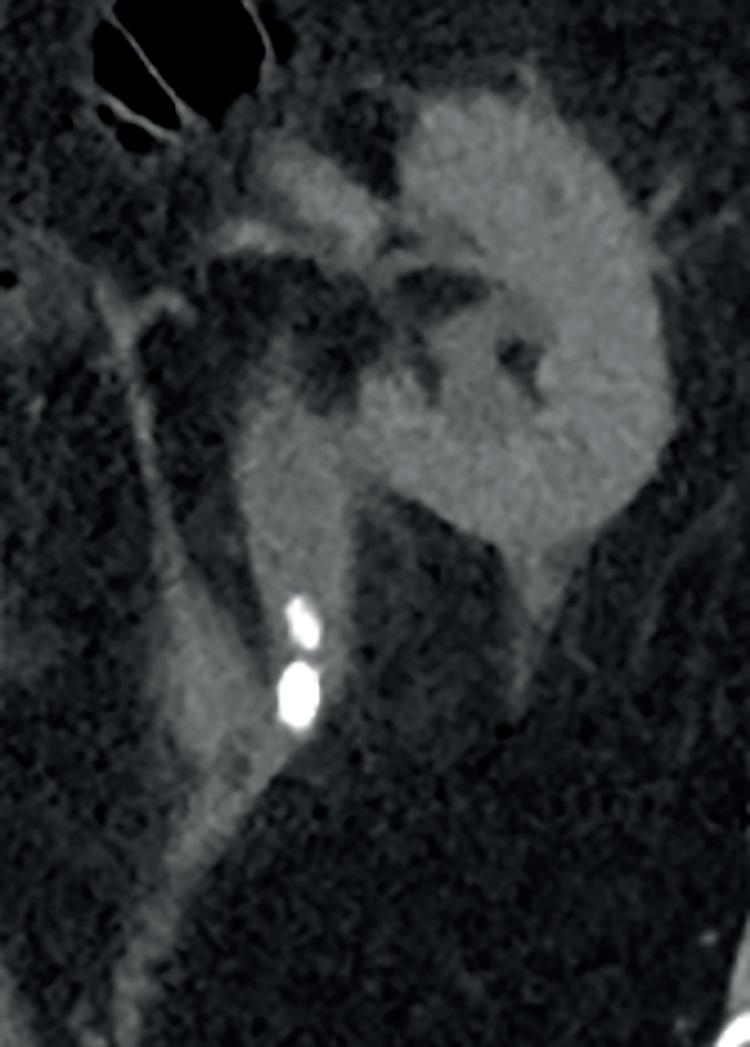

På intensivavdelingen lå en 21 år gammel kvinne som hadde kommet inn kvelden før med en skade i høyre nyre. Blødningen i nyren hadde stoppet av seg selv. Hovedproblemet var en åpen subtrokantær femurfraktur på høyre side med omfattende hud- og bløtdelstap fra hoften og ned til kneet. Hun skulle vært operert da hun kom inn, men det var det dessverre ikke kapasitet til. Nå hadde hun hemoglobin på 7 g/100 ml og var febril. På operasjonsstua debriderte vi så godt det lot seg gjøre og la et calcaneusstrekk for å stabilisere frakturen. Men vi var for sent ute, skulle det vise seg. Etter tre uker med gjentatte debridementer fikk vi henne ikke infeksjonsfri. Da ble benet eksartikulert i hofteleddet, og deler av hoftekammen som lå eksponert, ble meislet bort. Til tross for denne behandlingen døde hun etter hvert av sepsis. Vi kunne kanskje fått et annet resultat hvis vi hadde gjort et omfattende debridement ved innkomst.

En spesiell pasient har fulgt meg gjennom flere av mine opphold i Nepal. Jeg traff ham første gang i 2018. Han hadde fått kvestet høyre ben av en stor stein omtrent ti år tidligere. Pasienten ble den gang sendt til Kathmandu for å få behandlet benet sitt. Med lappeplastikk på leggen, delhudstransplantasjoner og margnagling av femur fikk man reddet underekstremiteten, men dessverre satt han igjen med en osteomyelitt i høyre distale femur (Bilde 2). Han ble reoperert flere ganger i ettertid, men til ingen nytte. Det var vedvarende sekresjon av illeluktende puss (penicillin-sensitive Staphylococcus aureus) fra dorsalt på låret. Vi, ved sykehuset i Okhaldhunga, reviderte benet hans på nytt med en lokal sekvestrektomi (fjerning av dødt benvev - sekvester) og S53P4 bioaktive glass- implantasjon (4,5). Dessverre hjalp dette bare i noen måneder. Deretter var infeksjonen tilbake igjen. Om alkoholproblemet hans kom før eller etter ulykken vet jeg ikke, men det hjalp heller ikke med tanke på etterlevelse av instruksjonene han fikk.

behandling Pasienten innfant seg ikke med dette og oppsøkte derfor på nytt sykehuset i Okhaldhunga i 2022 for en ”second opinion”. Det var da jeg traff ham for andre gang. Vi fant at pasienten hadde to fistelganger, den ene secernerende, og på nytt et sekvester dorsalt i distale femur. Pasienten fikk beskjed om at vi ville gi ham en siste sjanse. Det kunne bli en stor operasjon under to betingelser: Han måtte ta antibiotika tablettene sine etter operasjonen og dersom det ble et problem i forløpet måtte vi få lov å amputere benet. Det sa han ja til. Noen dager senere var vi i gang med operasjonen – via lateral subvastus tilgang til dorsale distale femur ble det utført saucerisasjon (fjerning av kortikalt ben og sekundær bentilheling) av hele bakre distale femur sirkumferens, margboring mot proksimalt og kyrettasje, i tillegg til margboring mot distalt (6). Heldigvis hadde jeg med meg en meget flink nepali kirurg som gjorde en møysommelig eksisjon av begge fistelgangene (Bilde 3). Vi la bølgedren i sårhulene og gjorde primær lukking. Pasienten fikk postoperativt kloksacillin i.v. 2 g x 4 i to uker, deretter dikloksacillin 1 g x 4 i fire uker (7). Han ble også instruert i å avstå fra vektbæring på høyre ben i rundt seks måneder, samt at han måtte bruke en stabiliserende kneortose for å forhindre fraktur av en tydelig svekket rørknokkel.